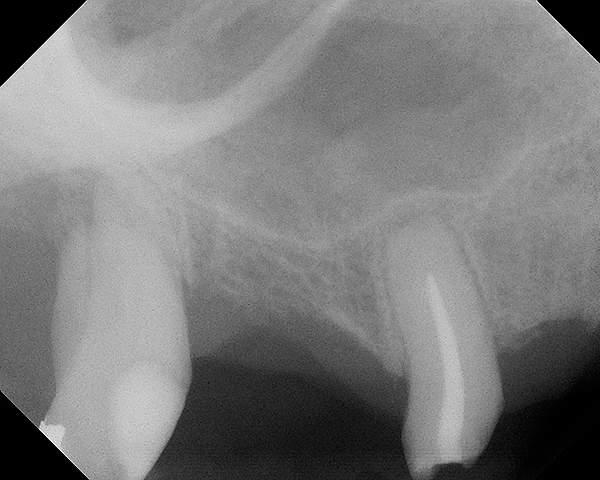

Fig 20. Case 3. Preoperative radiograph showing about 3.5 mm of ridge height.

Figure 20

Fig 21. Day of sinus augmentation and implant placement in the No. 3 position. The sinus membrane has been raised about 7 mm to 8 mm.

Figure 21

Fig 23. 6.5-month postoperative radiograph. Teeth Nos. 2 and 4 have been extracted and an immediate implant had been placed in the No. 4 position.

Figure 23

This patient was a 73-year-old man with only about 3.5 mm of native bone in the No. 3 site (Figure 20). The composite graft used here was a 50:50 mixture of DFDBA and deproteinized bovine bone mineral (Osteohealth, www.osteohealth.com) with approximately 40% calcium sulfate added. The implant was the same type and length as in Case 1 above. Figure 21 shows the area on the day of placement. In the CBCT scan on the day of placement (Figure 22), the native bone and bone graft were clearly discernable. However, the postoperative radiograph taken at 6.5 months (Figure 23) showed no marginal bone loss and a significantly denser appearance than when the graft was place. The membrane was raised about 7 mm to 8 mm. The final radiograph was taken after extraction of tooth No. 2 and after extraction of tooth No. 4 and immediate implant placement.